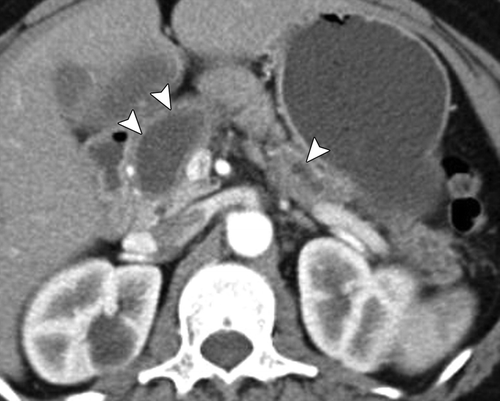

In all patients, a hyperenhancing mass was seen in the pancreas at the point of ductal transition. The lesions were most commonly located in the head of the gland, but the tumors can be present in the body or tail of the pancreas [9, 10, 13]. Tumor size, as measured at CT, ranged from 7 mm to 1.5 cm. Most of the tumors were smaller than 1 cm in diameter (Figs. 2A, 2B, 2C, 2D, 3A, 3B, 5A, 5B, 5C, 5D, 5E, 5F, 6A, 6B, 6C, and 6D). The tumor was usually visualized as a hyperenhancing lesion relative to the normal pancreatic parenchyma. Peak enhancement was seen during the arterial phase (25 seconds from the start of IV contrast injection in our protocol) (Figs. 4A, 4B, 4C, 6A, 6B, 6C, and 6D) or the portal venous phase (55–60 seconds) (Figs. 1A, 1B, 2A, 2B, 2C, 2D, 3A, 3B, 5A, 5B, 5C, 5D, 5E, and 5F); it can be more conspicuous in the arterial phase or the portal venous phase. Occasionally, the mass may not be well seen on CT images, and only segmental ductal dilatation or pancreatic atrophy is seen [10].

In this study, the pancreas was considered atrophic when the anteroposterior diameter of the pancreatic parenchyma excluding the pancreatic duct was less than 15 mm on axial images. Pancreatic atrophy was more pronounced in some cases (Figs. 1A, 1B, 2A, 2B, 2C, and 2D), and in other cases dilatation of the main pancreatic duct was more apparent than pancreatic atrophy (Figs. 3A, 3B, 4A, 4B, 4C, 5A, 5B, 5C, 5D, 5E, and 5F). Downstream of the ductal transition, the pancreas is usually of normal size. Distant metastasis (Figs. 1A and 1B) and adenopathy may be found. Small tumors usually do not involve the common bile duct; biliary ductal dilatation was not found in our cases.